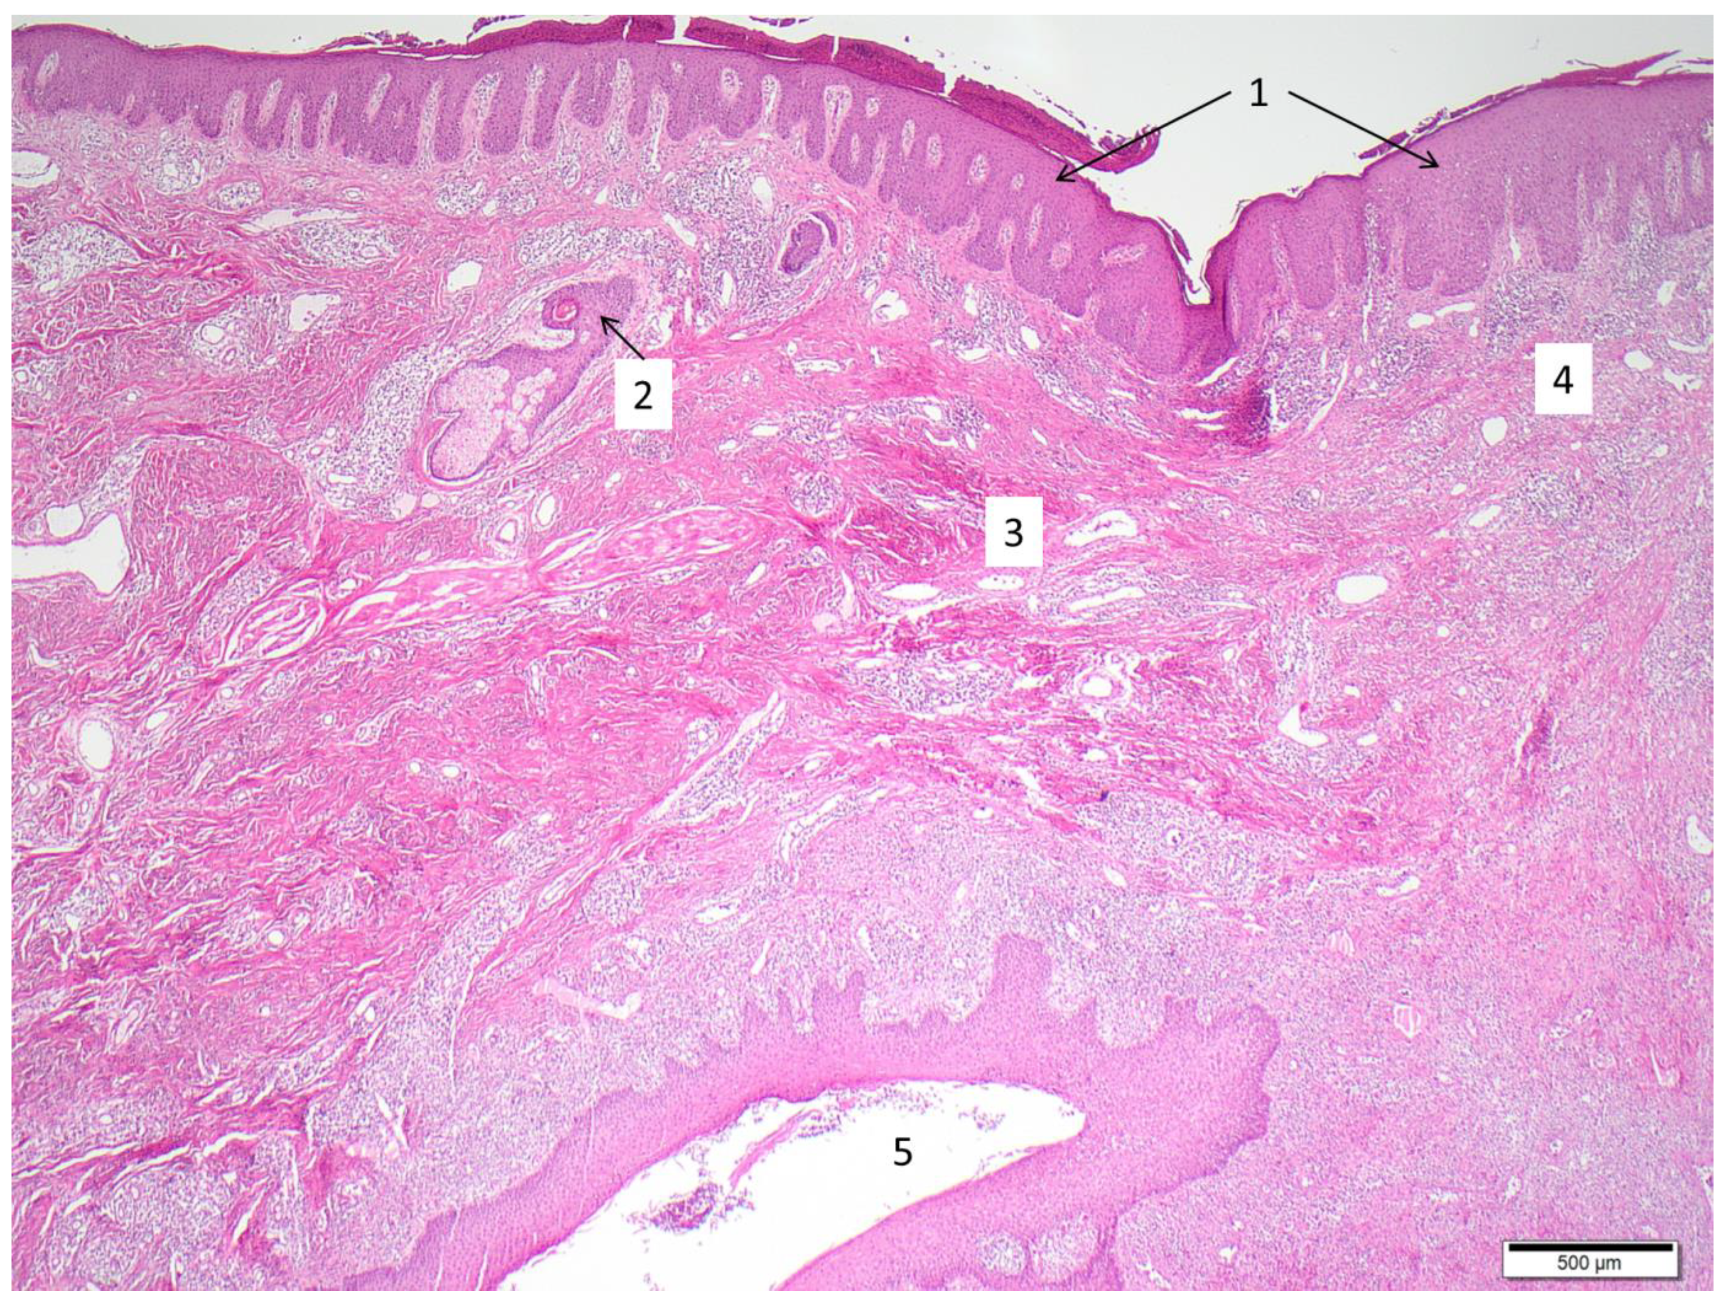

- von Laffert, M.; Helmbold, P.; Wohlrab, J.; Fiedler, E.; Stadie, V.; Marsch, W.C. Hidradenitis suppurativa (acne inversa): Early inflammatory events at terminal follicles and at interfollicular epidermis. Exp. Dermatol. 2010, 19, 533–537. [Google Scholar] [CrossRef] [PubMed]